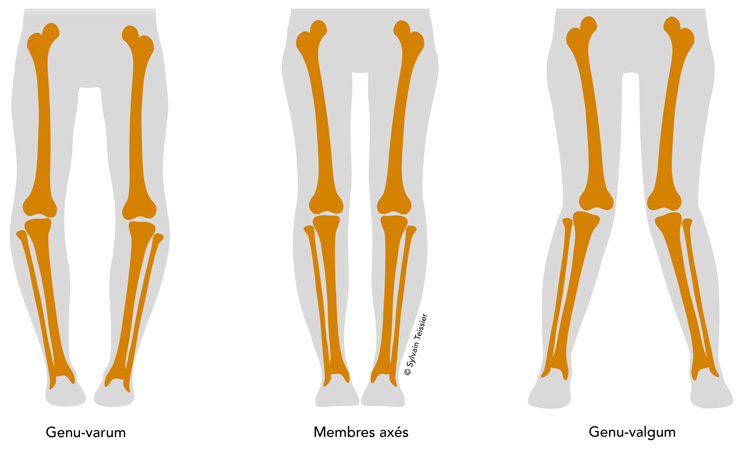

Indication d’ostéotomie pour ré-axer le genou.

On réalise une ostéotomie tibiale car la déformation est localisée sur le tibia, avec une plaque interne.

Arthrose externe, patiente jeune, genou en valgus (jambes en X), patiente jeune, on propose une ostéotomie pour ré-axer le genou.